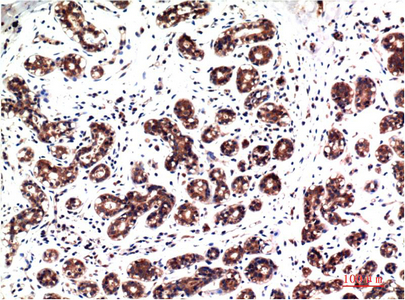

Main InformationTargetERK 1/2Host SpeciesMouseReactivityHuman, Rat, MouseApplicationsIHC, IFMW44,42kD (Observed)Conjugate/ModificationPhosphoDetailed InformationRecommended Dilution RatioIHC 1:100-200; IF 1:50-200FormulationLiquid in PBS containing 50% glycerol, 0.5% BSA and 0.02% sodium azide.SpecificityPhospho-ERK 1/2 (Y222/205)protein detects endogenous levels of MAPK1/MAPK3PurificationThe antibody was affinity-purified from mouse ascites by affinity-chromatography using specific immunogen.Storage-15°C to -25°C/1 year(Do not lower than -25°C)Concentration1 mg/mlMW(Observed)44,42kDModificationPhosphoClonalityMonoclonalClone Number4G3Antigen&Target InformationImmunogen:Synthetic Peptide of Phospho-ERK 1/2 (Y222/205) at AA range of 140-220Specificity:Phospho-ERK 1/2 (Y222/205)protein detects endogenous levels of MAPK1/MAPK3Gene Name:MAPK1/MAPK3Protein Name:MAPK1/MAPK3Other Name:MAPK1/MAPK3Background:The protein encoded by this gene is a member of the MAP kinase family. MAP kinases, also known as extracellular signal-regulated kinases (ERKs), act in a signaling cascade that regulates various cellular processes such as proliferation, differentiation, and cell cycle progression in response to a variety of extracellular signals. This kinase is activated by upstream kinases, resulting in its translocation to the nucleus where it phosphorylates nuclear targets. Alternatively spliced transcript variants encoding different protein isoforms have been described. [provided by RefSeq, Jul 2008],Function:Catalytic activity:ATP + a protein = ADP + a phosphoprotein.,cofactor:Magnesium.,Domain:The TXY motif contains the threonine and tyrosine residues whose phosphorylation activates the MAP kinases.,enzyme regulation:Activated by tyrosine phosphorylation in response to insulin and NGF.,Function:Involved in both the initiation and regulation of meiosis, mitosis, and postmitotic functions in differentiated cells by phosphorylating a number of transcription factors such as ELK-1. Phosphorylates EIF4EBP1; required for initiation of translation. Phosphorylates microtubule-associated protein 2 (MAP2). Phosphorylates SPZ1 (By similarity). Phosphorylates heat shock factor protein 4 (HSF4).,PTM:Dually phosphorylated on Thr-202 and Tyr-204, which activates the enzyme.,similarity:Belongs to the protein kinase superfamily.,similarity:Belongs to the protein kinase superfamily. CMGC Ser/Thr protein kinase family. MAP kinase subfamily.,similarity:Contains 1 protein kinase domain.,subunit:Interacts with MORG1 (By similarity). Binds to HIV-1 Nef. This interaction inhibits its kinase activity. Interacts with HSF4 and NISCH.,Cellular Localization:Cytoplasm . Nucleus. Membrane, caveola . Cell junction, focal adhesion . Autophosphorylation at Thr-207 promotes nuclear localization (PubMed:19060905). PEA15-binding redirects the biological outcome of MAPK3 kinase-signaling by sequestering MAPK3 into the cytoplasm (By similarity). .Tissue Expression:Epithelium,Eye,Hepatoma,Human cervix,Lymph,Research Areas:>>EGFR tyrosine kinase inhibitor resistance ; >>Endocrine resistance ; >>Platinum drug resistance ; >>MAPK signaling pathway ; >>ErbB signaling pathway ; >>Ras signaling pathway ; >>Rap1 signaling pathway ; >>cGMP-PKG signaling pathway ; >>cAMP signaling pathway ; >>Chemokine signaling pathway ; >>HIF-1 signaling pathway ; >>FoxO signaling pathway ; >>Sphingolipid signaling pathway ; >>Phospholipase D signaling pathway ; >>Oocyte meiosis ; >>Autophagy - animal ; >>mTOR signaling pathway ; >>PI3K-Akt signaling pathway ; >>Apoptosis ; >>Cellular senescence ; >>Adrenergic signaling in cardiomyocytes ; >>Vascular smooth muscle contraction ; >>TGF-beta signaling pathway ; >>Axon guidance ; >>VEGF signaling pathway ; >>Apelin signaling pathway ; >>Osteoclast differentiation ; >>Focal adhesion ; >>Adherens junction ; >>Gap junction ; >>Signaling pathways regulating pluripotency of stem cells ; >>Platelet activation ; >>Neutrophil extracellular trap formation ; >>Toll-like receptor signaling pathway ; >>NOD-like receptor signaling pathway ; >>C-type lectin receptor signaling pathway ; >>Natural killer cell mediated cytotoxicity ; >>IL-17 signaling pathway ; >>Th1 and Th2 cell differentiation ; >>Th17 cell differentiation ; >>T cell receptor signaling pathway ; >>B cell receptor signaling pathway ; >>Fc epsilon RI signaling pathway ; >>Fc gamma R-mediated phagocytosis ; >>TNF signaling pathway ; >>Circadian entrainment ; >>Long-term potentiation ; >>Neurotrophin signaling pathway ; >>Retrograde endocannabinoid signaling ; >>Glutamatergic synapse ; >>Cholinergic synapse ; >>Serotonergic synapse ; >>Long-term depression ; >>Regulation of actin cytoskeleton ; >>Insulin signaling pathway ; >>GnRH signaling pathway ; >>Progesterone-mediated oocyte maturation ; >>Estrogen signaling pathway ; >>Melanogenesis ; >>Prolactin signaling pathway ; >>Thyroid hormone signaling pathway ; >>Oxytocin signaling pathway ; >>Relaxin signaling pathway ; >>Parathyroid hormone synthesis, secretion and action ; >>GnRH secretion ; >>Type II diabetes mellitus ; >>AGE-RAGE signaling pathway in diabetic complications ; >>Cushing syndrome ; >>Growth hormone synthesis, secretion and action ; >>Aldosterone-regulated sodium reabsorption ; >>Alzheimer disease ; >>Prion disease ; >>Pathways of neurodegeneration - multiple diseases ; >>Alcoholism ; >>Pathogenic Escherichia coli infection ; >>Shigellosis ; >>Salmonella infection ; >>Pertussis ; >>Yersinia infection ; >>Leishmaniasis ; >>Chagas disease ; >>Toxoplasmosis ; >>Tuberculosis ; >>Hepatitis C ; >>Hepatitis B ; >>Human cytomegalovirus infection ; >>Influenza A ; >>Human papillomavirus infection ; >>Human T-cell leukemia virus 1 infection ; >>Kaposi sarcoma-associated herpesvirus infection ; >>Human immunodeficiency virus 1 infection ; >>Coronavirus disease - COVID-19 ; >>Pathways in cancer ; >>Viral carcinogenesis ; >>Proteoglycans in cancer ; >>MicroRNAs in cancer ; >>Chemical carcinogenesis - receptor activation ; >>Chemical carcinogenesis - reactive oxygen species ; >>Colorectal cancer ; >>Renal cell carcinoma ; >>Pancreatic cancer ; >>Endometrial cancer ; >>Glioma ; >>Prostate cancer ; >>Thyroid cancer ; >>Melanoma ; >>Bladder cancer ; >>Chronic myeloid leukemia ; >>Acute myeloid leukemia ; >>Non-small cell lung cancer ; >>Breast cancer ; >>Hepatocellular carcinoma ; >>Gastric cancer ; >>Central carbon metabolism in cancer ; >>Choline metabolism in cancer ; >>PD-L1 expression and PD-1 checkpoint pathway in cancer ; >>Lipid and atherosclerosis